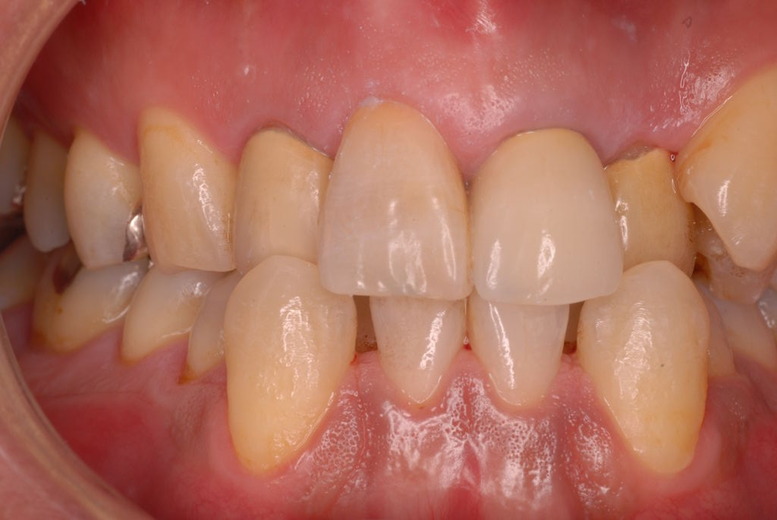

親知らずを取ることを嫌がる方が多いのですが、もし親知らずとその隣の14歳大臼歯の間に虫歯ができたり歯周病を罹患した場合、どれほど治療が大変で再発も起こりやすいか理解できない方がおおいのです。

写真左下の親知らずが痛くなり抜歯しました。その後歯茎を除去して虫歯を露出させる処置を二回ほどしています。

レントゲンでは小さいですが、こう言う虫歯が一番怖いのです。

治療の成功率は極めて悪くすぐ再発しやすいのです。

隣の14歳大臼歯がひどい虫歯になり治療不可能になりつつある状態のレントゲン